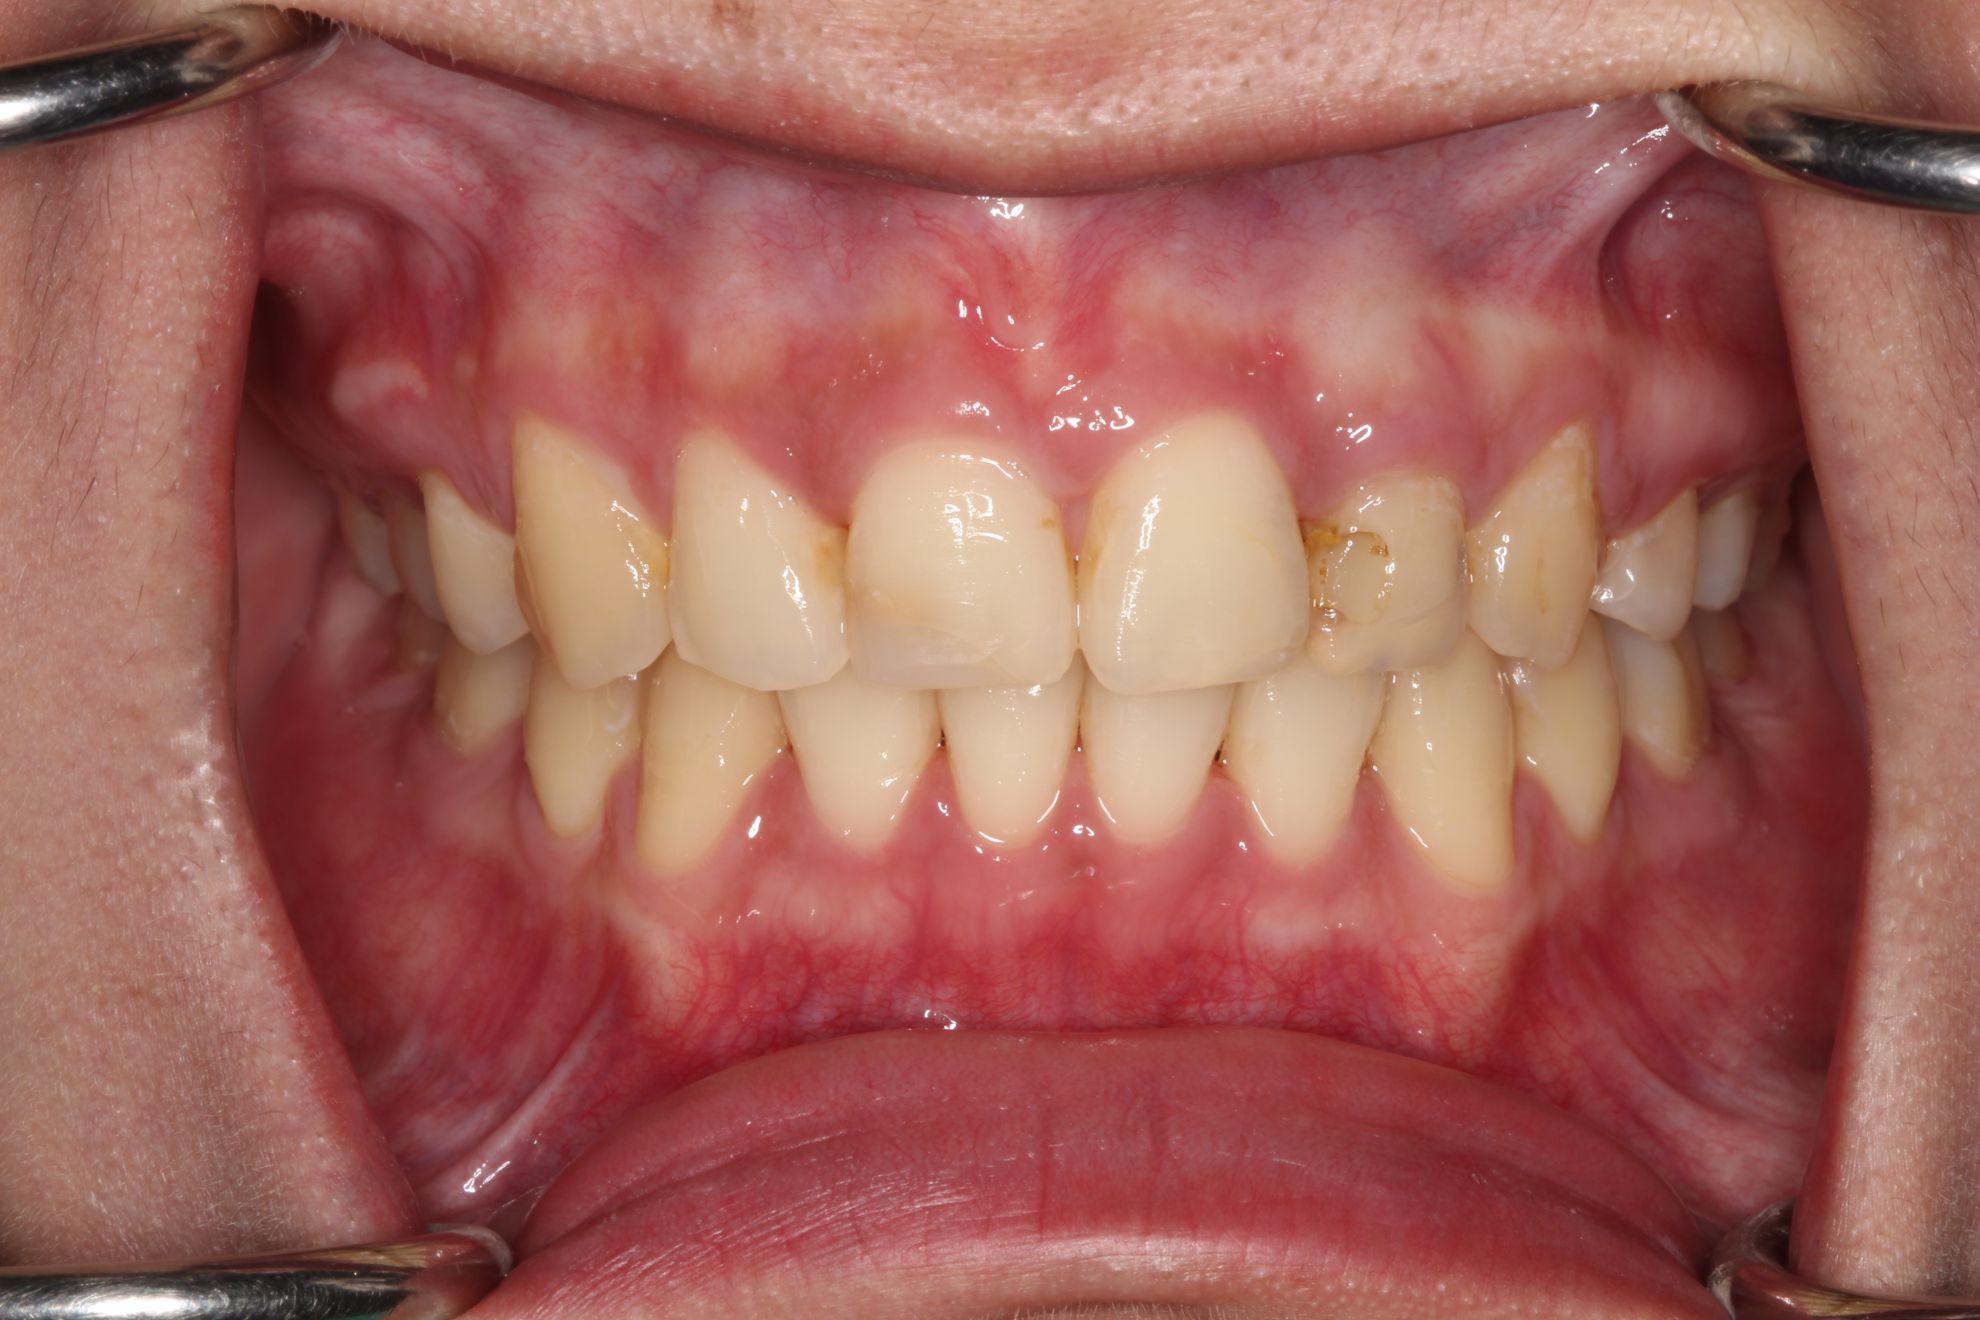

Before

• 牙齒暗黃

• 顏色不均

After

• 晶鑽居家美白

• 溫和美白不敏感

• 客製化專屬牙脫